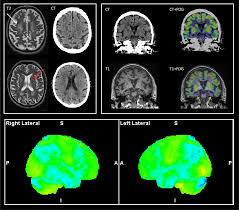

따라서 더욱 세밀하고 정확한 검사가 가능하며, CT검사로 찾아내지 못하는 질병을 발견할 수 있고, CT에 비해 정밀한 3차원 영상을 볼 수 있어 다양한 각도에서 질환을 판독하는데 용이하다고 한다. 주로 뇌, 신경, 혈관, 근육, 인대 등의 질병을 검사하고 진단한다고 한다.

그러나 MRI는 CT에 비해 출혈, 골절 등의 병변이 잘 보이지 않는 경향이 있어 응급상황에서는 최초 검사로 CT를 우선 시행하는 경우가 많고 세밀한 판독을 위한 추가 정밀검사 방법으로 MRI를 시행하게 된다고 한다. 한편 MRI는 근육파열, 신경손상 등을 확인하는데 효과적이고 특히 디스크 판독에도 탁월하다고 한다.